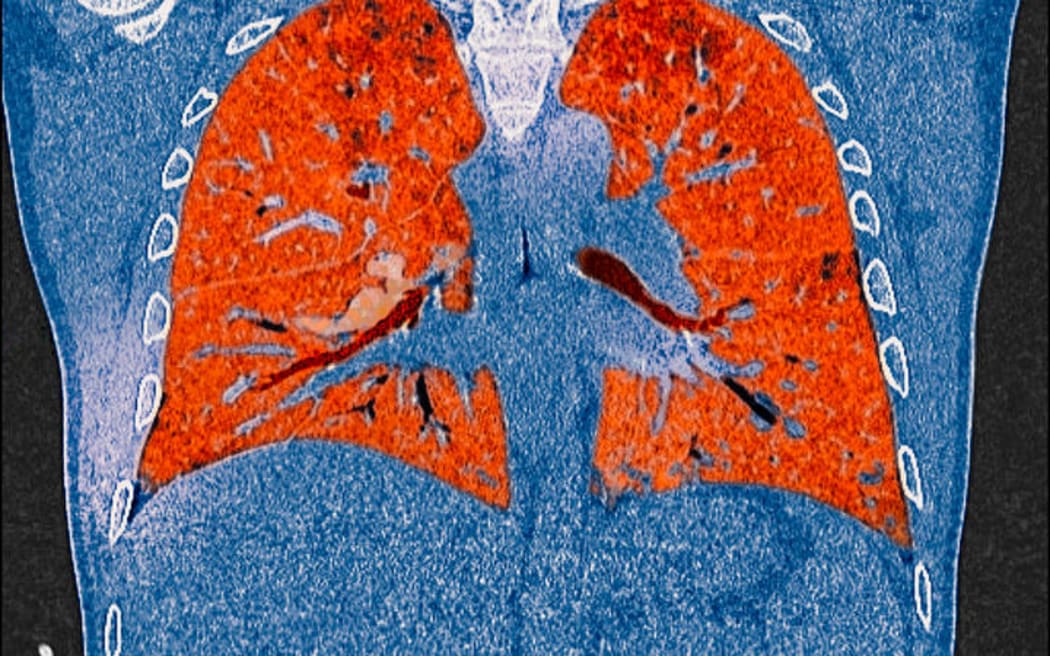

A CT scan of lungs showing the effects of Covid-19.

A CT scan of lungs showing the effects of Covid-19. Photo: AFP

Lingering symptoms such as crippling fatigue, "brain fog",  breathlessness, heart palpitations, chest pain and  aching muscles or joints are a grim reality for a subset of people infected with Covid-19.

Women are more likely to be affected than men and it can hit people whose infections were mild or who were asymptomatic.

Many of these Covid "long haulers" feel they are not being listened to by their doctors and have had their distress dismissed.